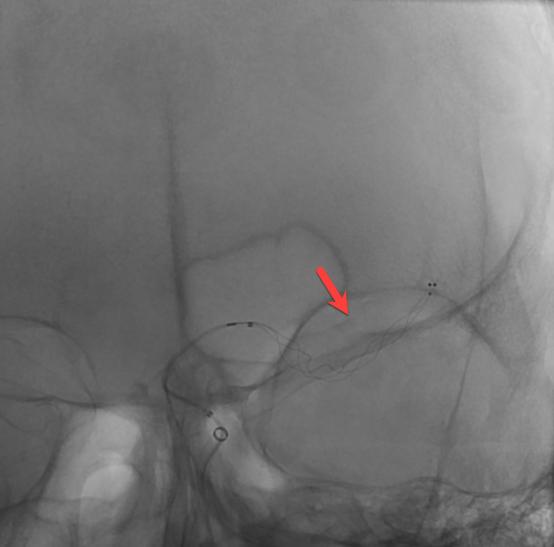

58岁的李大哥1周前有晕倒病史,但是没有到医院系统的治疗。发病前5个小时被人发现说不出话,右侧肢体不能活动。在我院神经内科急诊完善头颈部动脉CTA+CTP提示左侧大脑半球大片缺血带(图1)。是怎么回事呢?细心的血管介入科医生经过认真的分析图像,发现李大哥左侧颈内动脉存在的一个非常局限性的闭塞(图2、3),由于该段血管迂曲的走行在颅骨内不宜被发觉。得益于我院卒中团队的丰富经验,患者很快经绿色通道送至导管室准备手术。

在转运的过程中,患者症状持续加重,完全失语、右侧肢体全瘫同时意识逐渐模糊。糟糕,一定是左侧颈内动脉闭塞后血流缓慢继发颅内血栓形成。时间就是大脑,为挽救李大哥的生命,民航总医院卒中团队高效运作起来,神经内科、血管介入科、麻醉科迅速完成了患者的转运、麻醉及造影。如术前所料,患者左侧颈内动脉C6段闭塞(图4、5),左侧大脑中动脉M2段血栓形成(图6)。一个一个环环相扣的动作,一个一个精细无间的配合,血管介入科团熟练的完成了取栓支架就位(图7)、取出大脑中动脉血栓、植入颈内动脉支架(图8)等一系列操作,成功的开通了血管,恢复了颅内的血流(图9、10)。

图2

图3

图4

图5